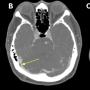

FIGURE 1: (A) Non-contrast CT brain demonstrated acute focal hemorrhage at the right occipital lobe withperihemorrhagic hypodensity extending to the right parieto-occipital region; (B) Subsequent CT venography in axial plane revealed thin linear isodensity within the right transverse sinus; (C) CT venography in coronal plane confirmed the filling defect within the right transverse sinus, consistent with thrombus

Case Report Page 542 - 546

Homonymous Hemianopia Associated with COVID-19 Vaccination